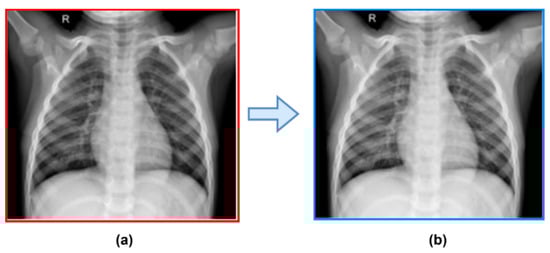

3.2.1. Pre-Processing